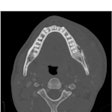

A new artificial intelligence (AI) model may provide support for detecting periapical lesions on cone-beam computed tomography (CBCT), according to a study published in the Journal of Dentistry.

Furthermore, the CBCT Segment Anything Model (SAM) may reduce human error and enable early detection of dental pathologies, the authors wrote.

"CBCT-SAM is capable of providing expert-level assistance in the identification of periapical lesions on CBCT," wrote the authors, led by Ka-Kei Chau of the University of Hong Kong (J Dent, December 10, 2024, Vol. 153, 105526).

Since periapical lesions are not always visible on radiographic scans, they may be missed. This occurrence can happen more often with less experienced dentists and when lesions are asymptomatic or are in the early stages. This is particularly true for CBCT scans with a large field of view.

Therefore, this study aimed to evaluate the effectiveness of CBCT-SAM in detecting periapical lesions on CBCT, they wrote.